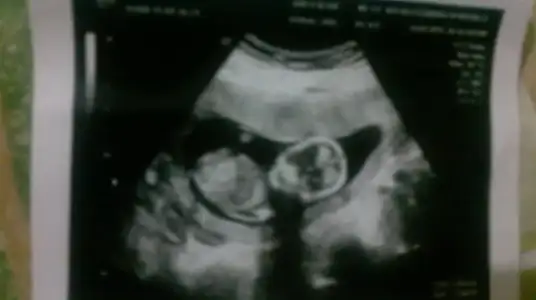

Kesin kiz diyorumMerhaba hamişler bende 12+2inci haftamdayım bugün ikili test için hastaneye gittim vee çıkıntınında belli olduğu güzel bi foto yakaladık yorumlarınız çok sevinirim canlar

Bence kızMerhaba hamişler bende 12+2inci haftamdayım bugün ikili test için hastaneye gittim vee çıkıntınında belli olduğu güzel bi foto yakaladık yorumlarınız çok sevinirim canlar